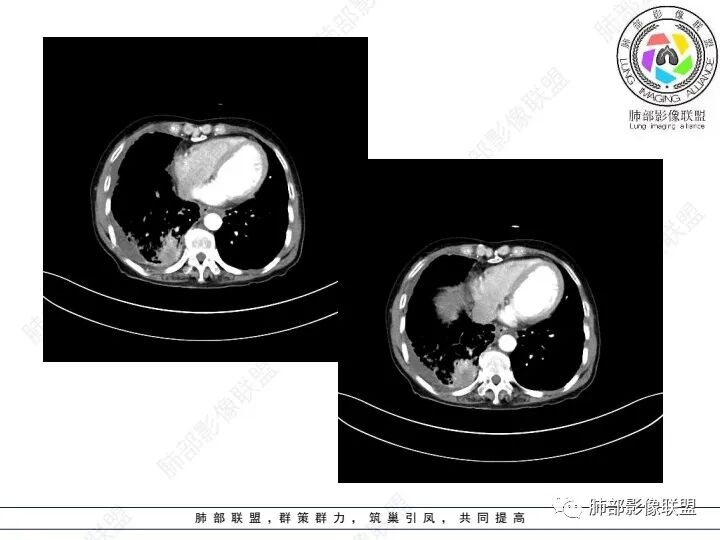

3、胸部增强CT示右肺下叶脊柱旁不规则软组织肿块,侵及壁层胸膜外,密度不均匀,不均匀强化,中心低密区可疑坏死,右侧胸腔积液、胸膜结节影或结节样增厚,增强扫描可见强化,右侧肺门及纵隔内可见淋巴结肿大、融合,右侧中尖段支气管及右肺下叶支气管受侵,管腔狭窄。

4、综上,老年男性,CA125升高,右肺下叶肿块侵犯胸壁,伴纵隔、右肺门及纵隔淋巴结肿大,右侧胸腔积液、胸膜增厚伴结节影,强化明显,应该为一较典型的肺癌伴肺胸膜腔及肺门纵隔淋巴结转移,尤其是肺腺癌。

1)由肺内侵及胸壁的块影,即提示其恶性生物学行为,也不为转移灶所常见。

4)转移灶多发但均限于右侧胸腔内,一般不符合远道而来的“双侧”。无论该患者有无腹腔或其他部位原发病灶。